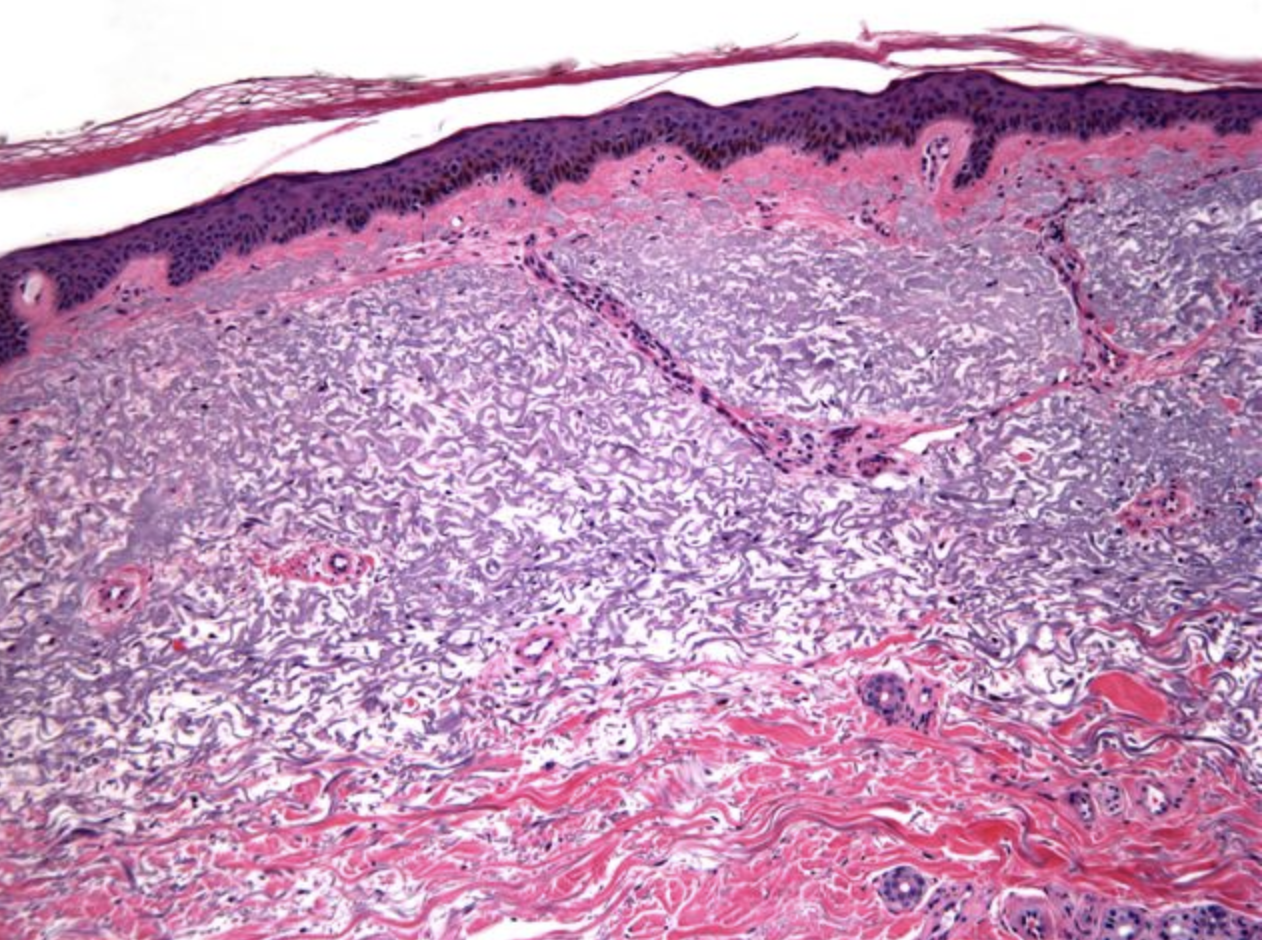

What are the histological manifestations of SCCs?

Generally “Pink” due to Keratin production

1. Pleomorphic epithelial cells (arising from epidermis, extending to dermis)

2. Keraton Pearls (central keratinization surrounded by concentric layer of abnormal squamous cells)